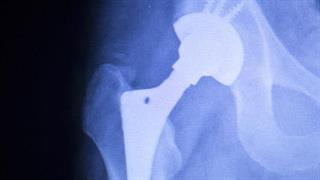

Ολική Αρθροπλαστική Ισχίου με την μέθοδο 'Superpath'

Τα τελευταία χρόνια, η ολική αρθροπλαστική έχει εισέλθει σε μια νέα εποχή. Με τη μέθοδο Superpath δεν γίνεται χειρουργική εξάρθρωση του ισχίου.

ΥΓΕΙΑ: Μέγιστη ακρίβεια και αποτελεσματικότητα στις επεμβάσεις γόνατος και ισχίου με το Ρομποτικό Σύστημα ΜΑΚΟ 2018

Το συγκεκριμένο σύστημα είναι το μοναδικό στην Ελλάδα.